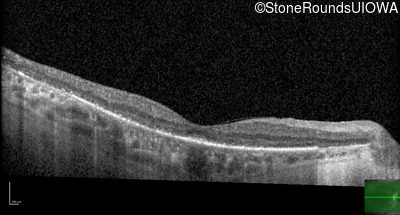

Age at visit: 59 years

This 59 year old woman has been night blind for as long as she can remember. She first noted constricted visual fields in her late 30s.